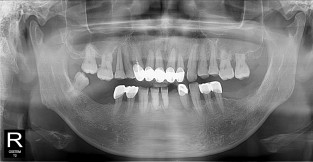

• 3

전체어금니

치료기간 : 2021-10-20 ~ 2023-08-31

1. 상기 x-ray 이미지 모두 동일한 해당 의료기관에서 진료한 환자입니다.

2. 상기 x-ray 이미지 모두 동일 인물의 것입니다.

3. 치료 전 이미지는 2021-10-20에 촬영했으며, 치료 후 이미지는 2023-08-31에 촬영하였습니다.

4. 상기 x-ray 이미지 모두 동일 조건에서 환자분의 동의를 받아촬영되었습니다.

* 임플란트 시술은 환자분의 상태(고혈압, 당뇨 등)에 따라 부작용이 있을 수 있으니, 반드시 전문의와 상담이 필요합니다.

* 임플란트 수술 부작용

: 수술 후 출혈, 교합, 통증, 붓기, 염증 등의 문제점이 발생할 수 있습니다.)